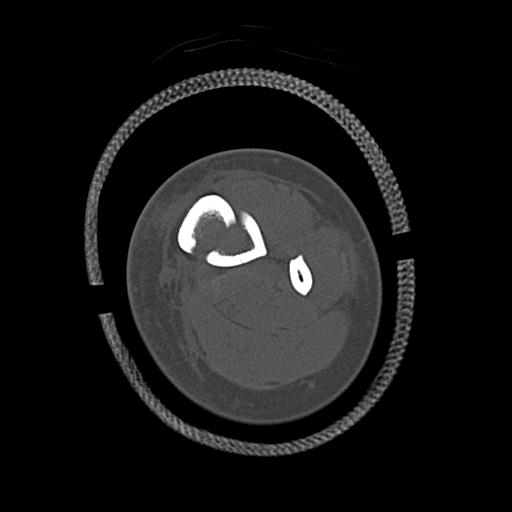

100612 11/25 1/20 右膝 2R 84歳女性 右TKA

91983 11/16 左膝 2R 11/18 2R 55歳男性 脛骨骨切り術